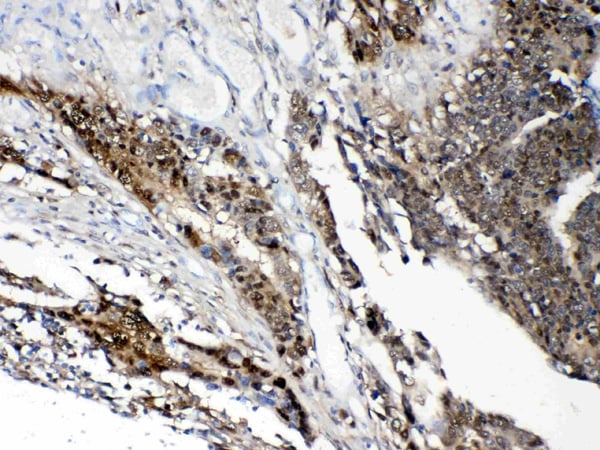

(Figure 2. IHC analysis of STAT1 using anti- STAT1 antibody (AAA124543).STAT1 was detected in paraffin-embedded section of human intestinal cancer tissues. Heat mediated antigen retrieval was performed in citrate buffer (pH6, epitope retrieval solution) for 20 mins. The tissue section was blocked with 10% goat serum. The tissue section was then incubated with 1ug/ml rabbit anti- STAT1 Antibody (AAA124543) overnight at 4 degree C. Biotinylated goat anti-rabbit IgG was used as secondary antibody and incubated for 30 minutes at 37 degree C. The tissue section was developed using Strepavidin-Biotin-Complex (SABC) with DAB as the chromogen.)